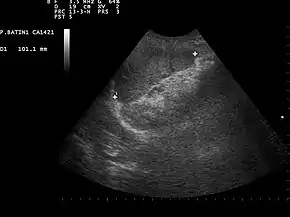

![]() Ultrasound image of a normal spleen that may be seen in part of the eFAST | |

- Left Upper Quadrant of the abdomen (Perisplenic view). Left upper quadrant is examined by working your probe down the midaxillary line starting at the left 8th rib to the 11th rib. This examines for free fluid around the kidney and spleen.